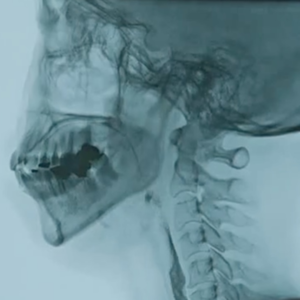

14:41 吞咽障碍的主要原因

18:08 胃造瘘术是不是吞咽障碍的最后的办法?

18:47 日剧《旅行护士》剧情中所讲述的“孤独美食家粉丝”吞咽障碍患者的康复过程和黎花医生的康复治疗过程可以说是一模一样。

*胃造瘘是指针对晚期食管癌患者,医生没有给他切去食管癌,而是仅在腹部留一根管子。临床上用得不少,是晚期食管癌姑息性治疗的一种,就是改善食管癌患者吃饭喝水的痛苦,同时尽最大能力达到治疗目的,延长生命!